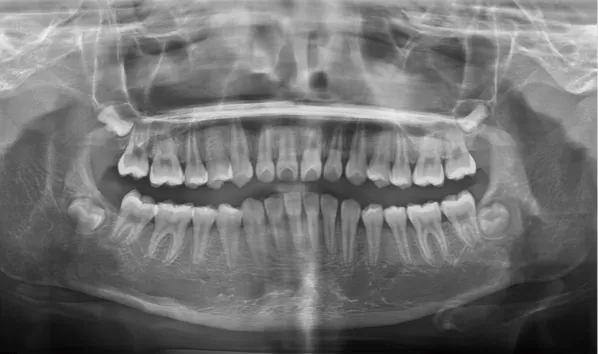

Rayons X avant le traitement

[Radiographie panoramique/Céphalogramme latéral]